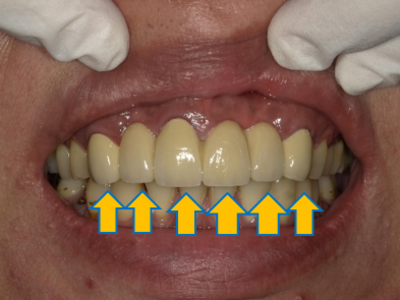

案例 2 術後(After)

門牙重建,改善牙縫過大問題